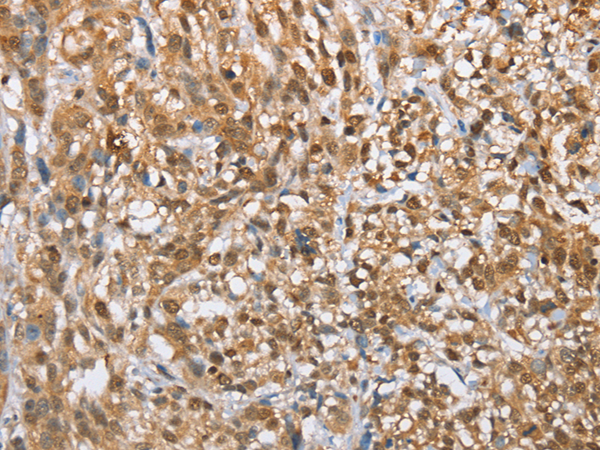

IHC positive control: |

Human thyroid cancer and human esophagus cancer |

IHC Recommend dilution: |

50-200 |